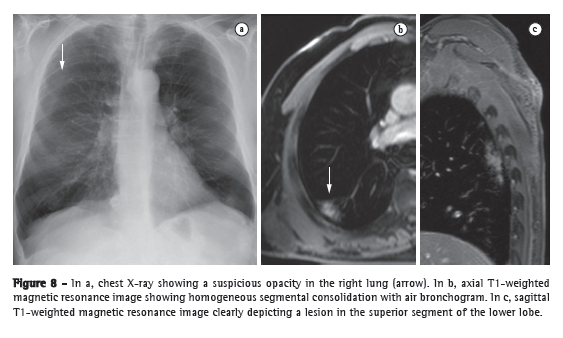

The various features of pneumonia, such as ill-defined nodules, ground-glass opacities, and consolidations, can be easily detected and differentiated with MRI. In chest X-ray, extremely small nodules and calcifications pose great challenges because of the thickness of the slice and the low intensity of the signal. As a follow-up tool, MRI is recommended over CT, in order to avoid excessive exposure to ionizing radiation. Figure 8 shows a comparison between a chest X-ray and MRI scans of the same chest. The sensitivity of T2-weighted sequences and the potential of contrast-enhanced T1-weighted sequences can greatly facilitate the differential diagnosis.(36) In addition, incipient complications, such as pericardial effusion, pleural effusion, empyema, and lung abscess, are easily recognized on MRI scans. In immunocompromised patients, MRI is nearly as accurate as is CT for the detection of pulmonary abnormalities.(8)